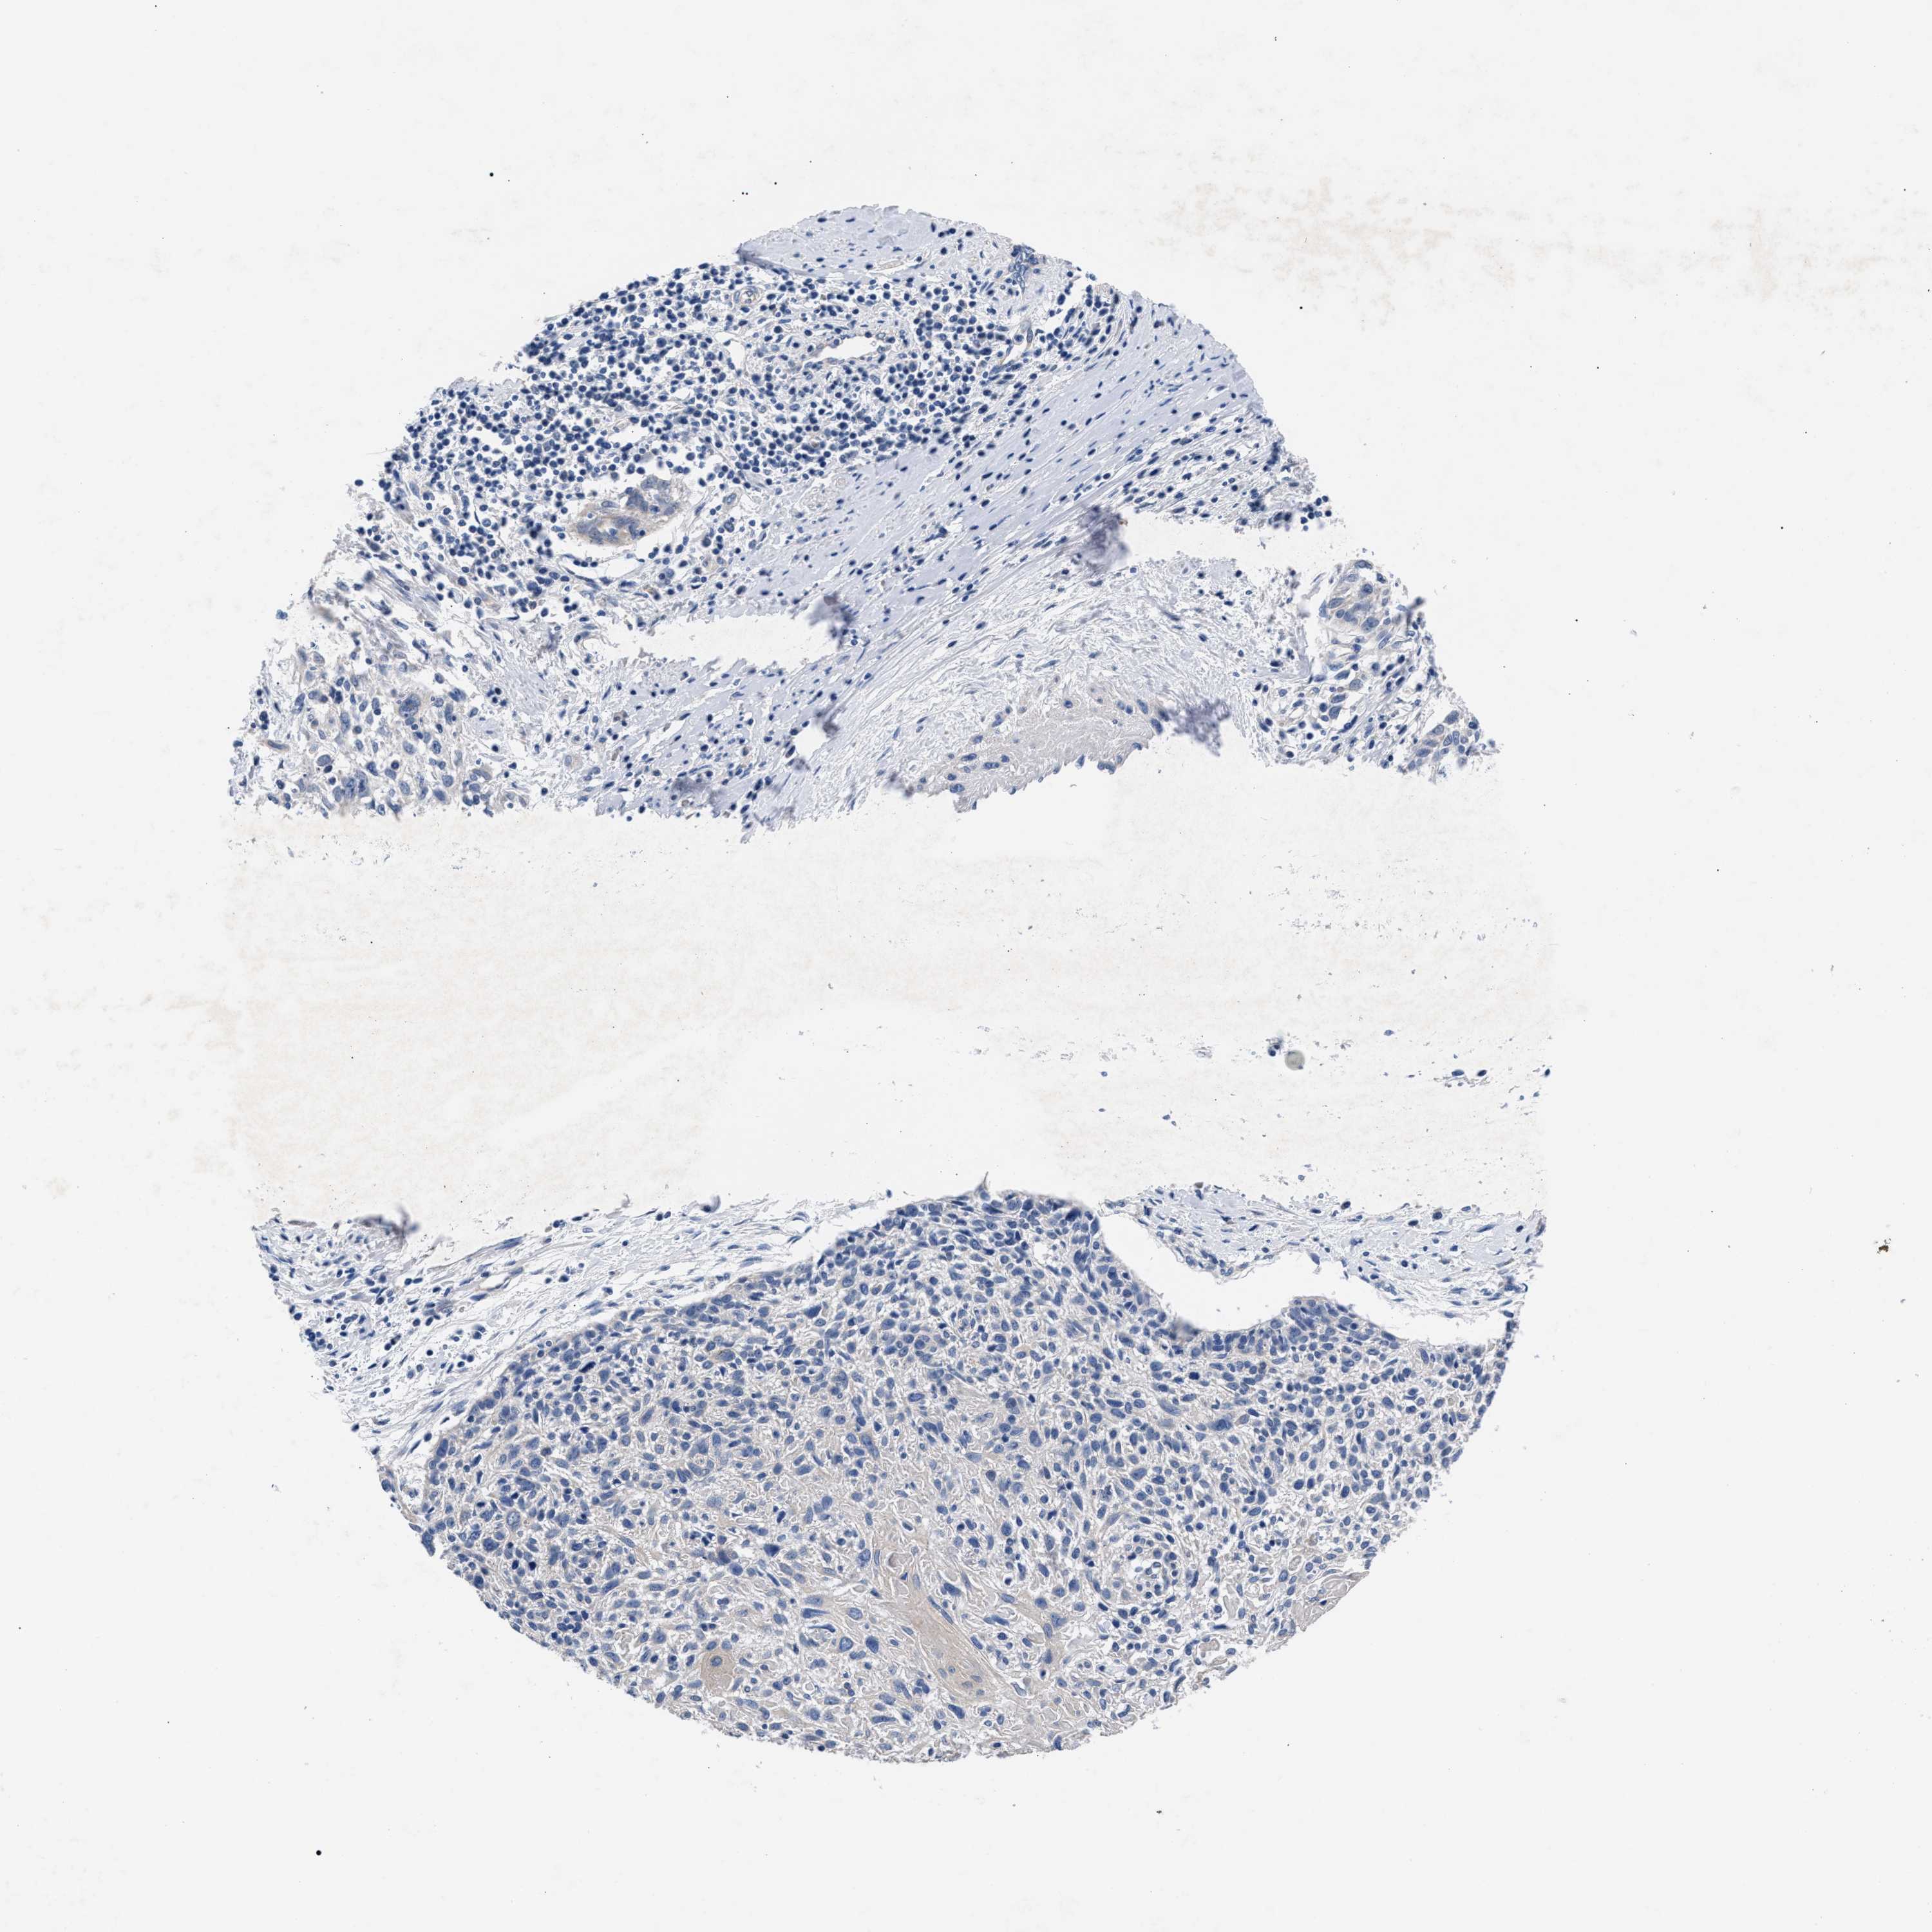

CERVICAL CANCER - Protein expressioni

A mouse-over function shows sample information and annotation data. Click on an image to view it in a full screen mode. Samples can be filtered based on level of antibody staining by selecting one or several of the following categories: high, medium, low and not detected. The assay and annotation is described here.

Note that samples used for immunohistochemistry by the Human Protein Atlas do not correspond to samples in the TCGA dataset.

Antibody stainingi

Antibody staining in the annotated cell types in the current human tissue is reported as not detected, low, medium, or high, based on conventional immunohistochemistry profiling in selected tissues. This score is based on the combination of the staining intensity and fraction of stained cells.

Each image is clickable and will lead to virtual microscopy that enables deeper exploration of all samples and also displays staining intensity scores, fraction scores and subcellular localization as well as patient and tissue information for each sample.

Antibody HPA020974

Staining

High

Medium

Low

Not detected

Intensity

Strong

Moderate

Weak

Negative

Quantity

>75%

75%-25%

<25%

None

Location

Nuclear

Cytoplasmic/membranous

Cytoplasmic/membranous,nuclear

Squamous cell carcinoma, NOS

Adenocarcinoma, NOS